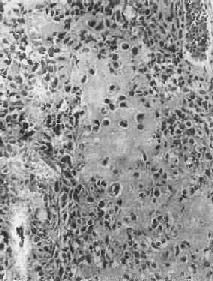

骨腫瘤組織學表現骨腫瘤最終診斷的完成有賴於組織學檢查,通常經常活檢術獲取組織標本。活檢術需要有經驗的醫生施行,要保證得到有診斷意義的組織。切口設計應照顧到後續手術,最低限度地減少腫瘤細胞的擴散及對鄰近正常組織的污染,決不可認為活檢術為小手術而輕率從之,取材應避開壞死區,多取幾個部位。腫瘤的外圍部分多為反應區,有時不足以作出肯定的診斷,但是,病理檢查也有其局限性,如疲勞骨折、骨化肌炎容易誤診為骨肉瘤;甲狀旁腺功能亢進時的棕色瘤易誤診為巨細胞瘤;軟骨來源的腫瘤難以區分良惡性等。